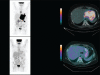

Accurate diagnosis and staging are essential for the optimal management of cancer patients. Positron emission tomography with 2-deoxy-2-[fluorine-18]fluoro-D-glucose integrated with computed tomography (18F-FDG PET/CT) has emerged as a powerful imaging tool for the detection of various cancers. The combined acquisition of PET and CT has synergistic advantages over PET or CT alone and minimizes their individual limitations. It is a valuable tool for staging and restaging of some tumors and has an important role in the detection of recurrence in asymptomatic patients with rising tumor marker levels and patients with negative or equivocal findings on conventional imaging techniques. It also allows for monitoring response to therapy and permitting timely modification of therapeutic regimens. In about 27% of the patients, the course of management is changed. This review provides guidance for oncologists/radiotherapists and clinical and surgical specialists on the use of 18F-FDG PET/CT in oncology.